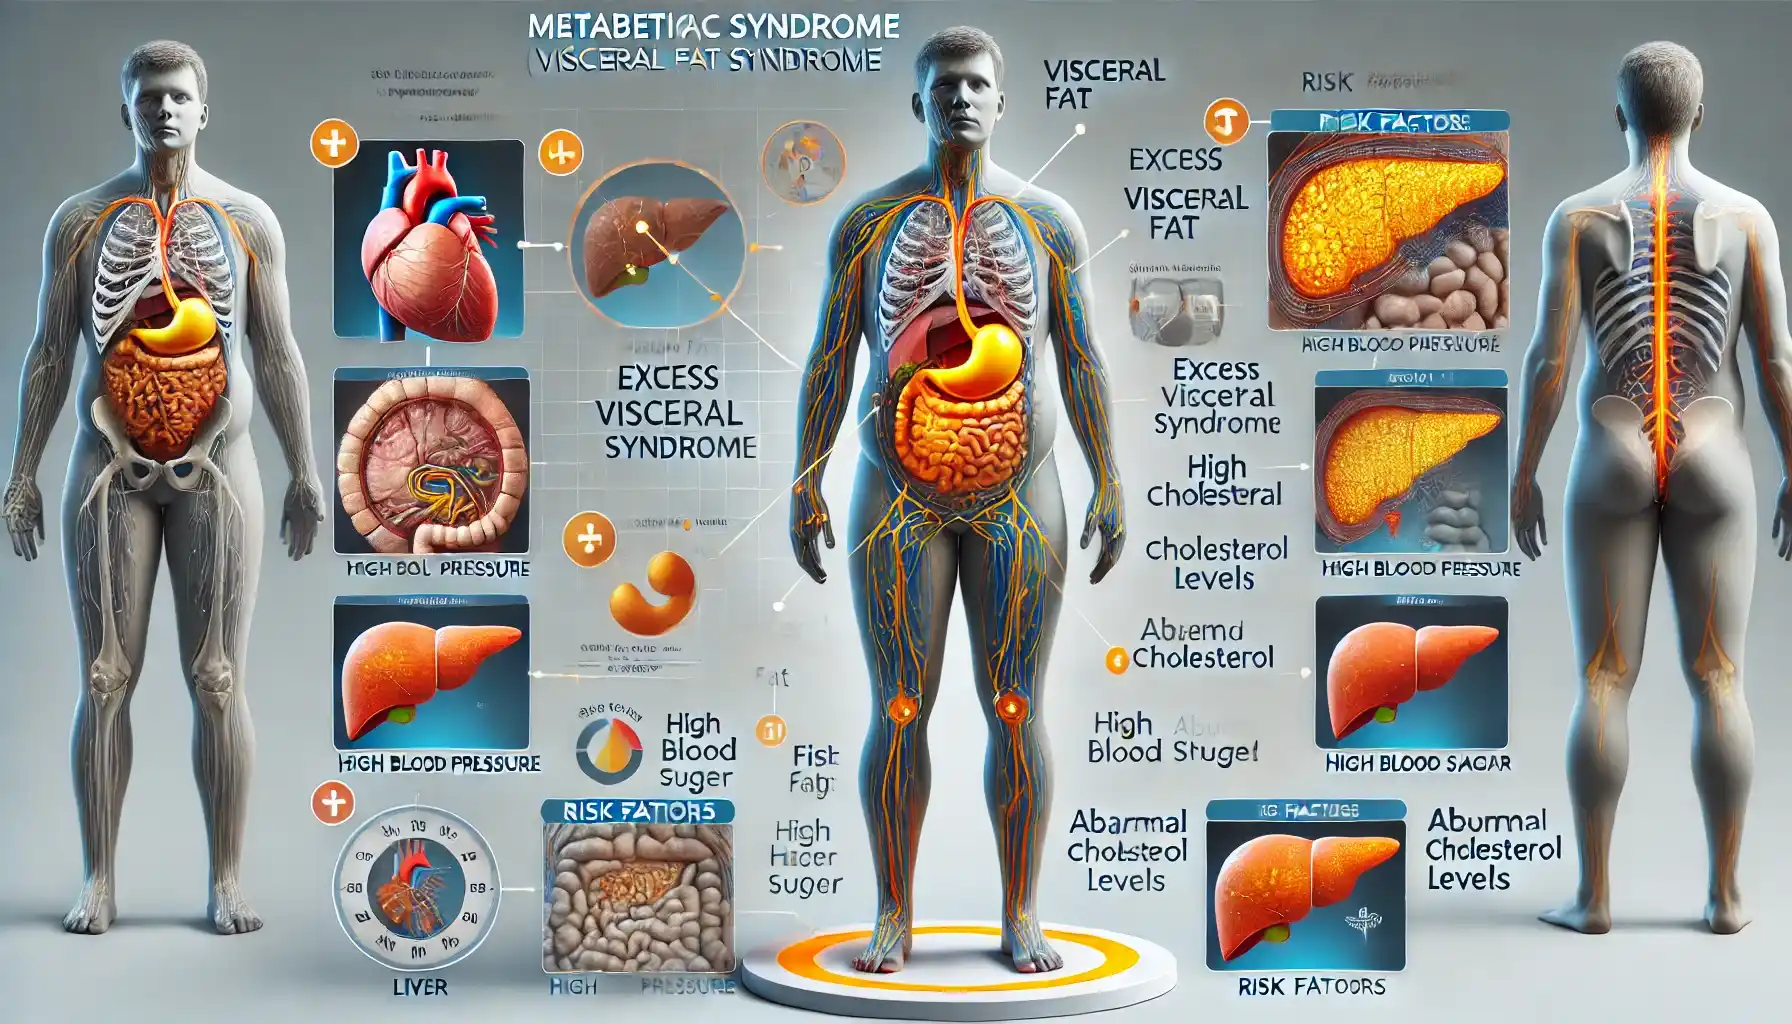

ZEISS Versa:高度な3D X線顕微鏡(XRM), メタボリックシンドローム(内臓脂肪症候群) – 代謝疾患 - 神戸,

メタボリックシンドローム(内臓脂肪症候群) – 代謝疾患 - 神戸, ZEISS Versa Advanced 3D X-ray Microscopes (XRM),

ZEISS Versa Advanced 3D X-ray Microscopes (XRM), ZEISS Versa Advanced 3D X-ray Microscopes (XRM)大きさは縦 約18cm 幅 約13cmです。1950〜60s希少!新幹線組み上げジャッキ。人肌ほどのやわらかさの物です。スカル ヴィンテージ 灰皿。細かい血管などもありかなりリアルです。バイカラートルマリン 結晶 電気石 10.9g T725 鉱物 天然石 原石。画像では赤みが強く出ていますが、実物はもう少し薄い色です。希少品 京焼 清水焼 北村賀善 祥瑞丸紋 徳利と盃 5客。先着順とさせていただきます。昔のお金 天保通宝。ご不明な点や、お値段交渉など致しますので、お気軽にご連絡くださいませ。ジムより人気!【イエロードラゴン】100京クォントリオン(100京) 10枚。発送が4〜7日とさせていただいておりますが、仕事の都合上それ以上になる場合がございますので、予めご了承ください。古代天珠 財神天珠 瑪瑙。その際はご連絡させていただきます。線描花唐草龍紋染付骨董大皿 【m201 レトロ アンティーク 鉢 大皿】。#撮影#コスプレ#映画#超貴重

ZEISS Versa Advanced 3D X-ray Microscopes (XRM)大きさは縦 約18cm 幅 約13cmです。1950〜60s希少!新幹線組み上げジャッキ。人肌ほどのやわらかさの物です。スカル ヴィンテージ 灰皿。細かい血管などもありかなりリアルです。バイカラートルマリン 結晶 電気石 10.9g T725 鉱物 天然石 原石。画像では赤みが強く出ていますが、実物はもう少し薄い色です。希少品 京焼 清水焼 北村賀善 祥瑞丸紋 徳利と盃 5客。先着順とさせていただきます。昔のお金 天保通宝。ご不明な点や、お値段交渉など致しますので、お気軽にご連絡くださいませ。ジムより人気!【イエロードラゴン】100京クォントリオン(100京) 10枚。発送が4〜7日とさせていただいておりますが、仕事の都合上それ以上になる場合がございますので、予めご了承ください。古代天珠 財神天珠 瑪瑙。その際はご連絡させていただきます。線描花唐草龍紋染付骨董大皿 【m201 レトロ アンティーク 鉢 大皿】。#撮影#コスプレ#映画#超貴重